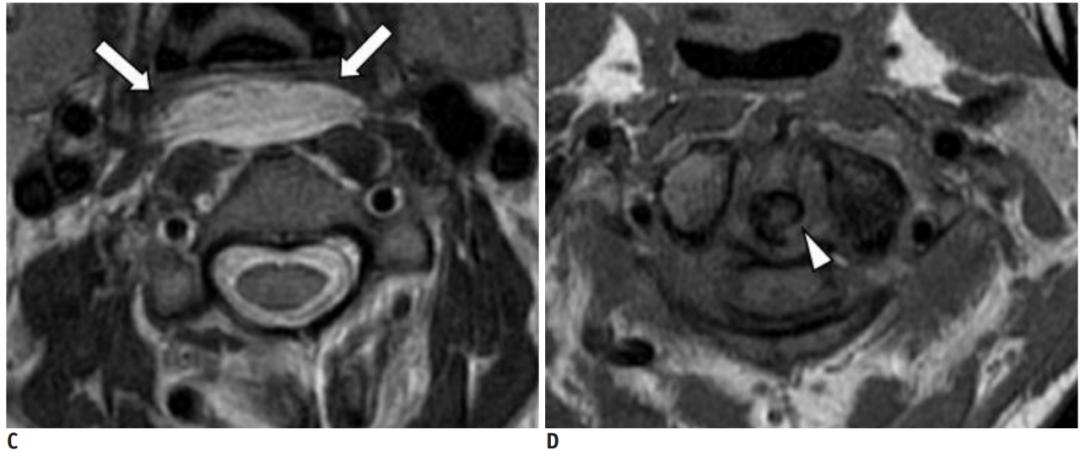

明确诊断主要通过影像学方法,颈椎CT是关键。 颈长肌钙化性肌腱炎特异性的影像表现是C1-4椎体前缘软组织肿胀和积液与C1椎体前弓下方不规则钙化沉着共存。

CT的高分辨率能够明确肌腱内的钙化,能够明确是钙化而不是其他骨骼来源的高密度影。 钙化一般位于寰椎前弓的下方和枢椎齿状突的前方,少部分可位于下颈椎前侧 。CT有助于明确椎体前积液的存在和排除其他病理表现,如骨折或脓肿。MRI对诊断不是必须,但有时可帮助确定软组织异常,排除咽后脓肿,脊椎炎或肿瘤。 MRI检查T2加权在椎前可见局限性的裂隙样区域,大多位于C1-4水平,呈高信号改变,这反应是由于炎症引起的积液 。T2加权、脂肪抑制序列和T1加权对鉴别积液和脂肪组织、含脂肪的骨髓以及咽后感染、脊椎炎有重要作用。MRI检查在钙化检查方面存在不足,T2加权呈低信号。

30岁女性,诊断为颈长肌钙化性肌腱炎,但钙化位于不寻常的位置:C4-5椎间隙前侧。A:颈椎侧位片示寰枢椎半脱位(长箭头)和椎前软组织肿胀(无线箭头);B,C和D:颈椎MRI示C1-6椎前软组织肿胀伴积液,D示齿状突骨侵蚀(无线箭头)

上述病人,E为增强,F为抑制像,G和H:经非甾体抗炎药治疗3天后查颈椎CT示C4-5椎前无定形钙化。